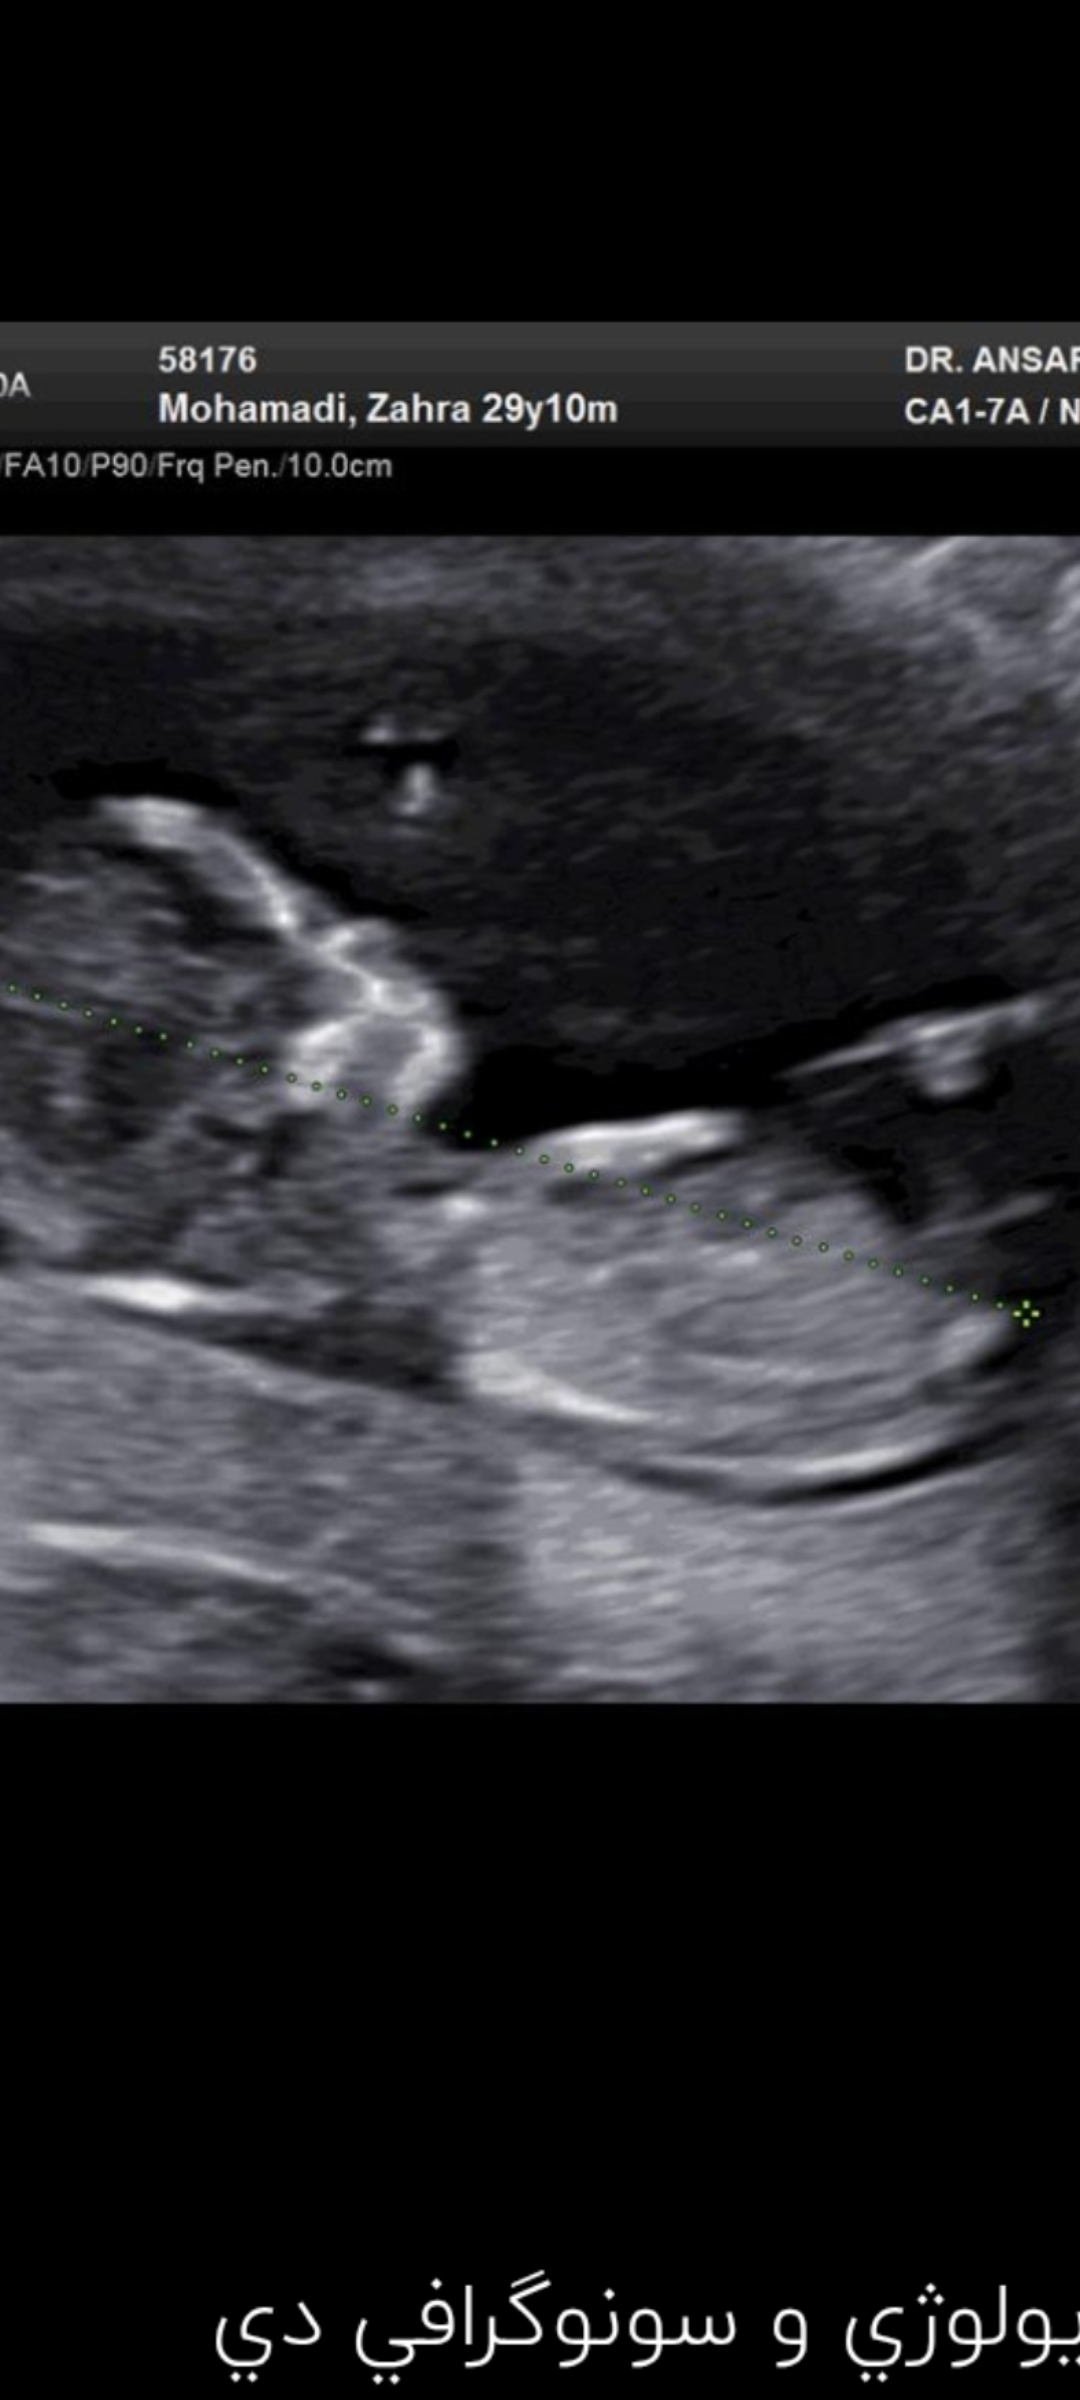

آنیییییییی مدیر استارتر عضویت: 1404/04/12 تعداد پست: 46 عنوان نی نی کوچولو 48 بازدید | 1 پست بچه ها دکتر به من احتمال جنسیت داده بنطرتون هفته۱۴جنسیت و میتونن دقیق بگن؟ 1404/04/15 | 01:47 0 نفر لایک کرده اند ... گزارش تاپیک نامناسب